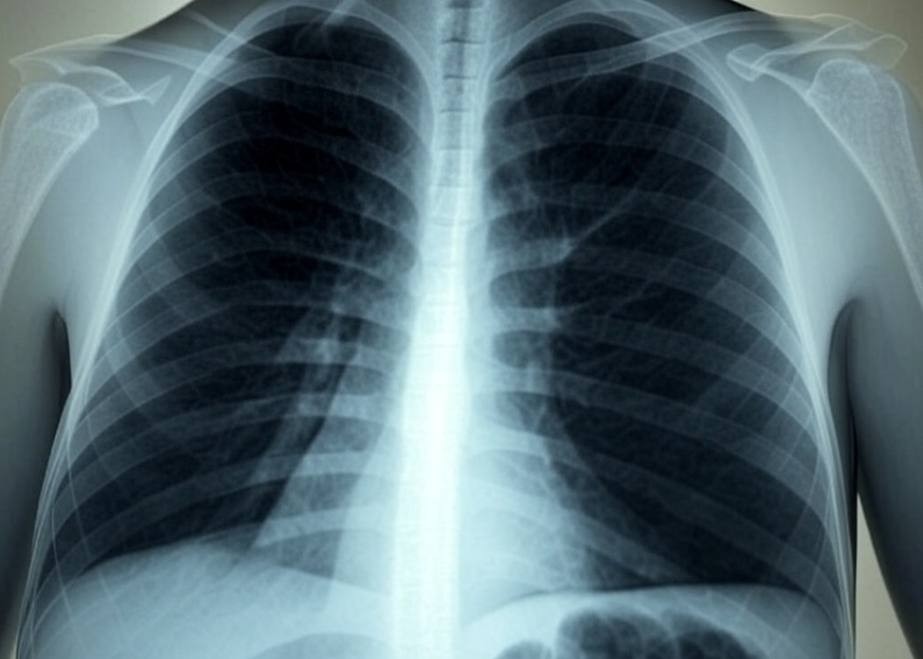

The 100-day intensified TB elimination campaign was launched on December 7, 2024 across 455 intervention districts in 33 States and Union Territories to screen and test for TB among people belonging to the vulnerable or high-risk group — diabetics, smokers, alcoholics, people living with HIV, those with TB in the past, geriatric population, house-hold contacts of TB patients. Besides screening people who have TB symptoms, the main intent of the intensified campaign is to use a chest X-ray to screen people for subclinical or asymptomatic TB disease followed by bacteriological confirmation using a molecular test.

“This isn’t just about diagnosing patients who show symptoms; it’s about finding those hidden cases who would otherwise remain undetected by using Chest X-rays, enhanced with AI, an effective method for screening individuals who may have TB but may not have the classical symptoms of TB,” Dr. Vinod Paul, Member of Niti Aayog wrote in an Opinion article in Business Line on March 5, 2025.

As per the National TB Prevalence Survey 2019-2021, 42.6% of TB cases would have been “missed” if a chest X-ray was not used for screening, thus revealing the magnitude of subclinical/asymptomatic TB cases in India. To detect such cases, the campaign claimed that a “new strategy was designed” for early identification of TB by using X-ray for screening people without TB symptoms. Yet, only 38 lakh of the over 10 crore (100 million) individuals have been screened using X-rays as of February 22, which is just 3.8%. Worse, despite the fact that asymptomatic TB disease cases can be detected only with a chest X-ray, all the 38 lakh people screened using a chest X-ray did not belong to this category. As per the press release, only a “substantial population” of people without TB symptoms were screened with a chest X-ray. Though it claims “several asymptomatic TB patients” are detected, there is no mention of the actual numbers.